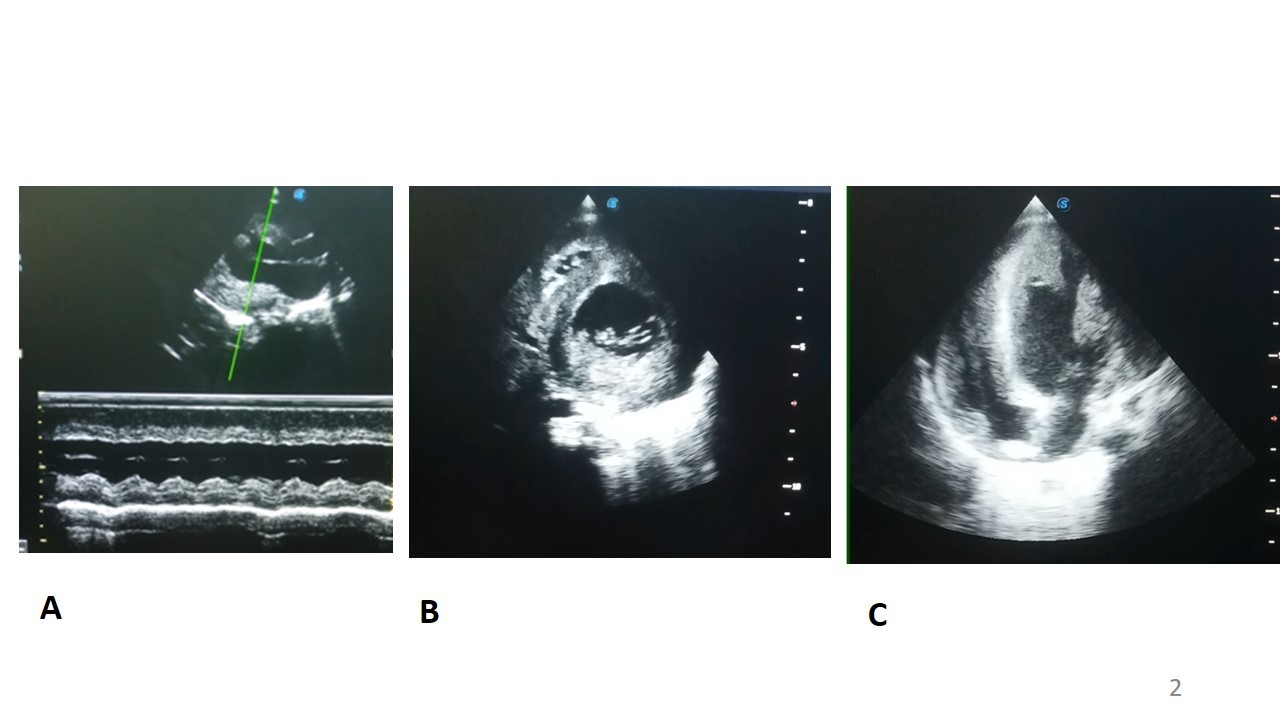

A l’échocardiographie Doppler (figure 4) on retrouvait une hypertrophie biventriculaire importante, plus marqué sur le ventricule gauche (septum interventriculaire en diastole de 10 mm, paroi postérieure en diastole de 10mm), une altération de la fonction systolique ventriculaire gauche (FEVG mesuré en Simpson bi-plan à 30%). Les cavités cardiaques gauches étaient dilatées.

Figure 4 : Echocardiographie Doppler chez un enfant de 10 mois, porteur de maladie de la

Pompe infantile et d’un albinisme oculo-cutané.

A : mode TM en parasternal grand axe, montrant une hypertrophie concentrique du ventricule gauche avec septum intreventriculaire et paraoi postérieure mesurée en diastole à 10 mm

B : mode 2D en parasternal court axe, montrant une hypertrophie concentrique du ventricule gauche

C : mode 2D en apical 4 cavités montarnt une hypertrophie bi ventriculaire importante